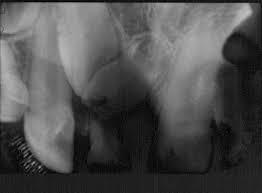

Doble exposicióo Causado por tomar la misma radiografía dos veces. Se ven varias imágenes de dientes sobrexpuestos.